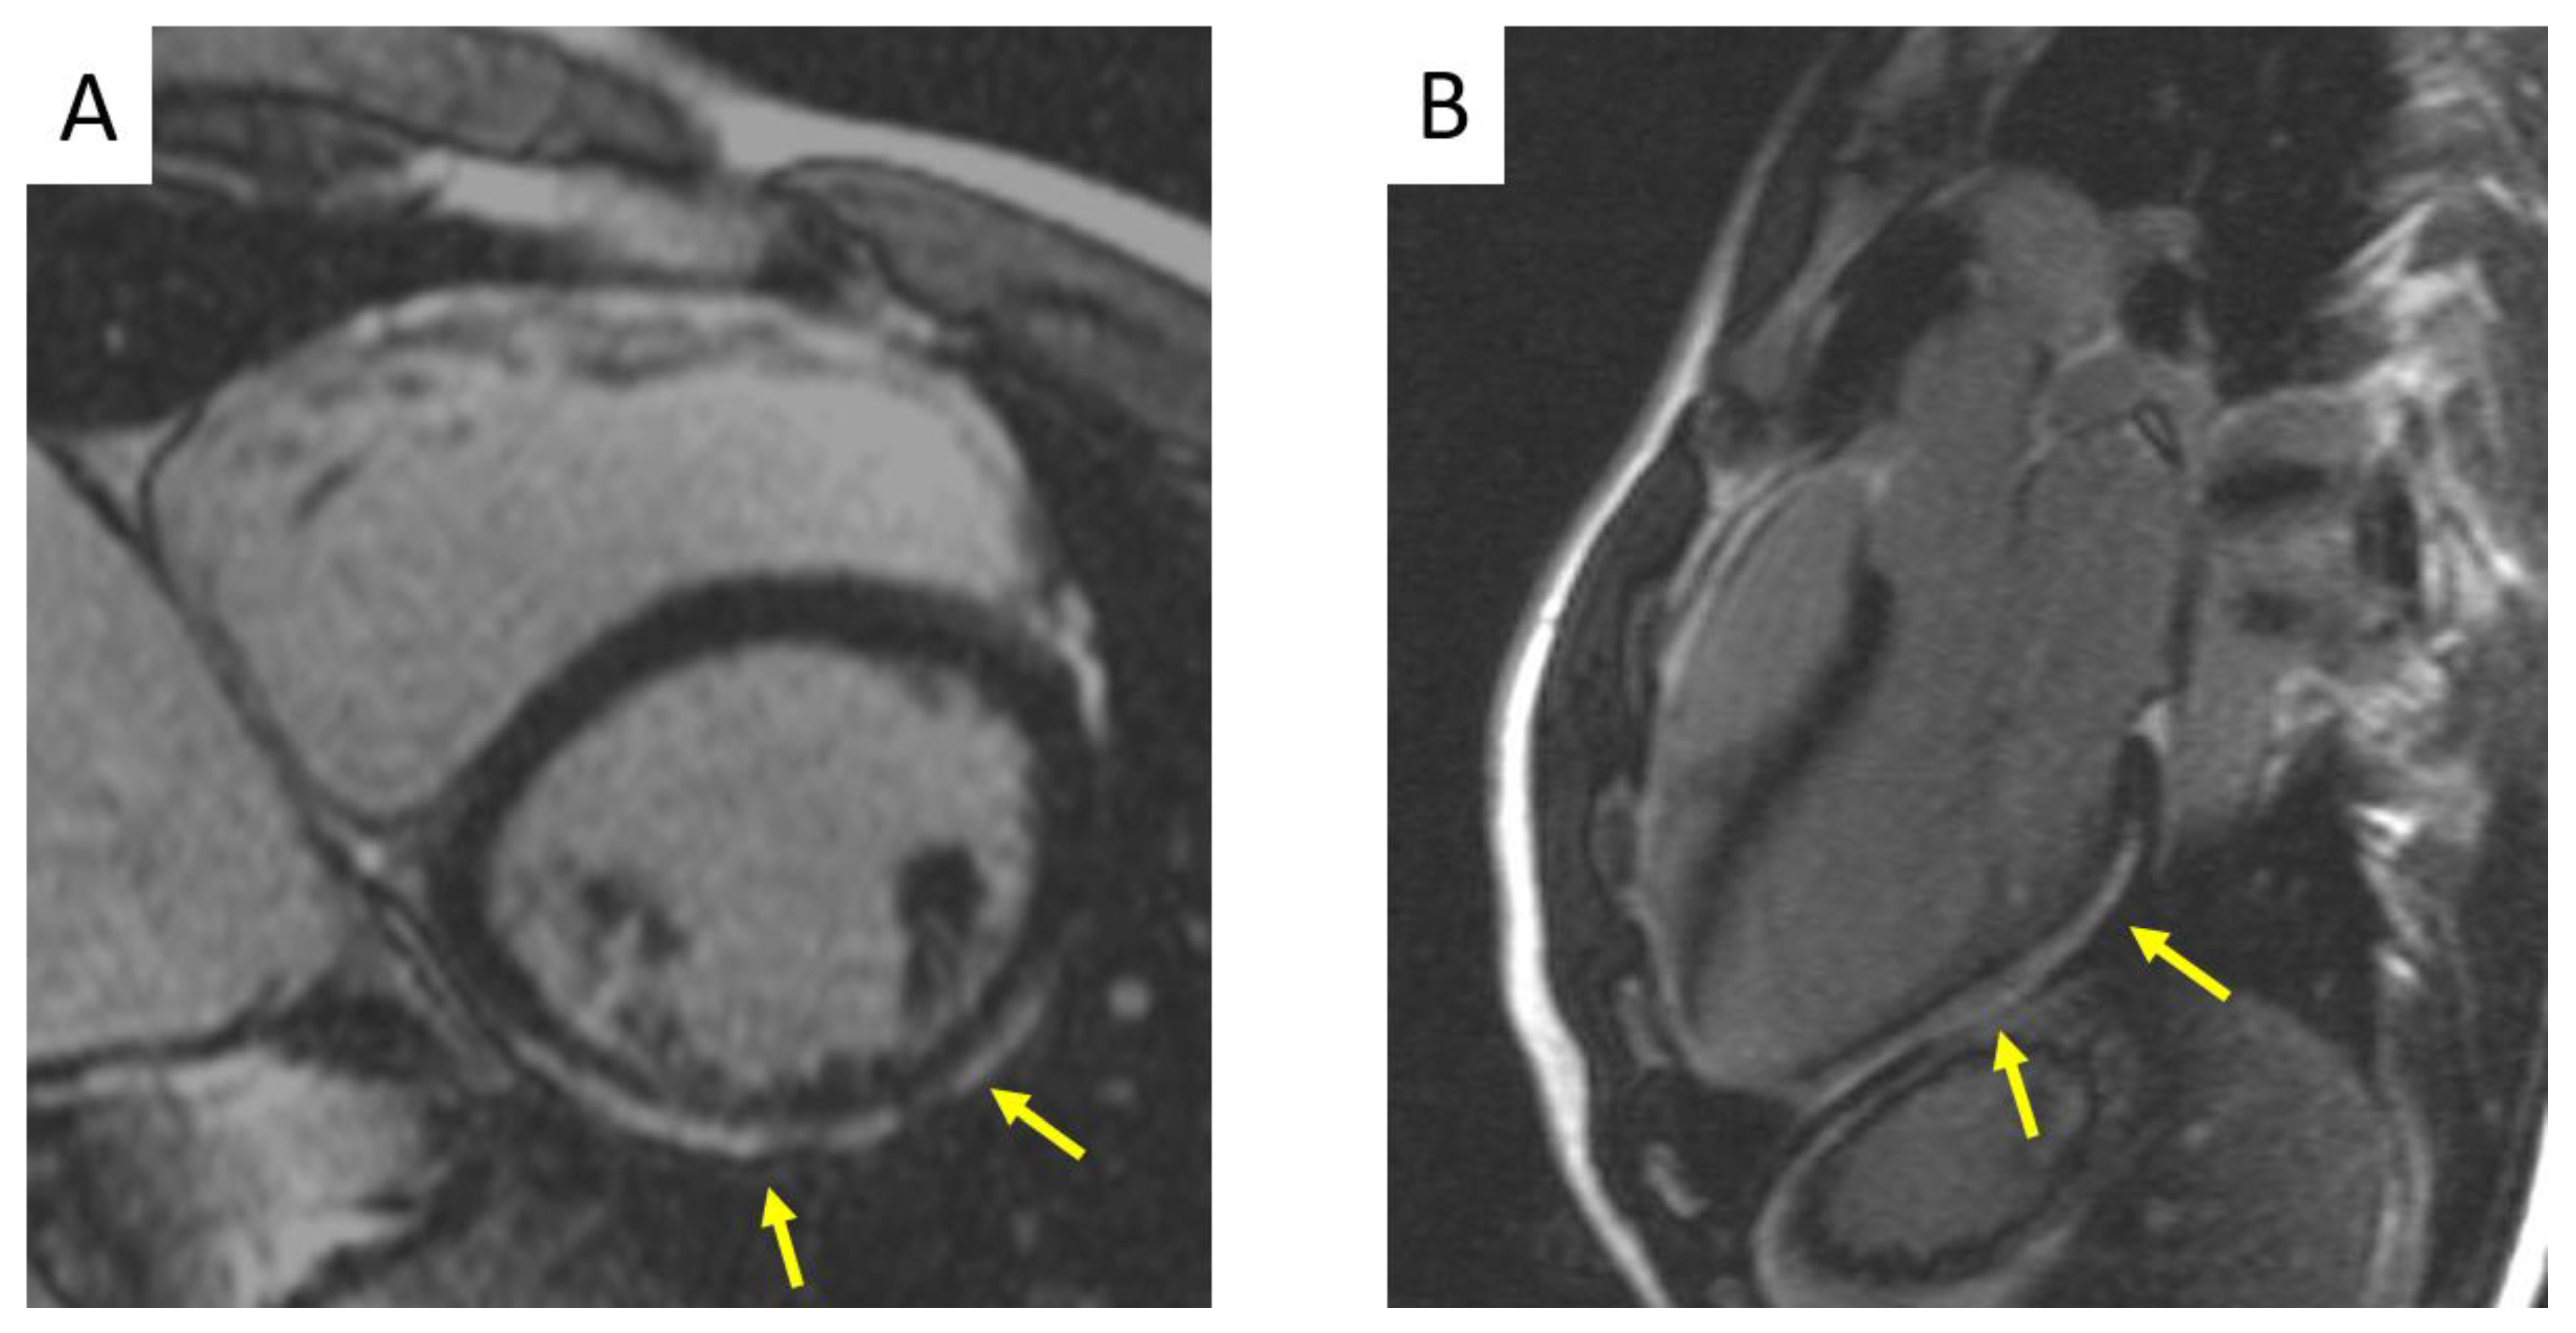

- Corrado, D.; Perazzolo Marra, M.; Zorzi, A.; Beffagna, G.; Cipriani, A.; Lazzari, M.; Migliore, F.; Pilichou, K.; Rampazzo, A.; Rigato, I.; et al. Diagnosis of arrhythmogenic cardiomyopathy: The Padua criteria. Int. J. Cardiol. 2020, 319, 106–114. [Google Scholar] [CrossRef]

- Pontone, G.; Di Bella, G.; Castelletti, S.; Maestrini, V.; Festa, P.; Ait-Ali, L.; Masci, P.G.; Monti, L.; Di Giovine, G.; De Lazzari, M.; et al. Clinical recommendations of cardiac magnetic resonance, Part II. J. Cardiovasc. Med. 2017, 18, 209–222. [Google Scholar] [CrossRef] [PubMed]